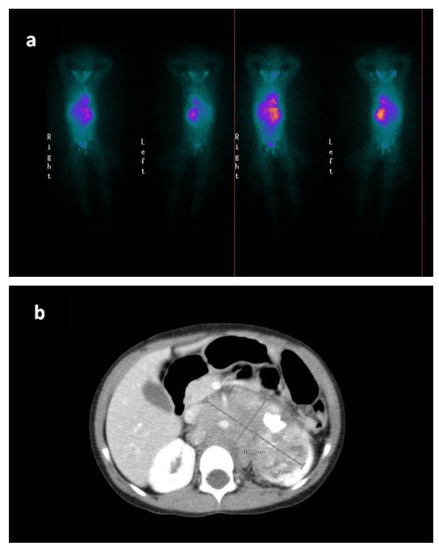

2. Case Report